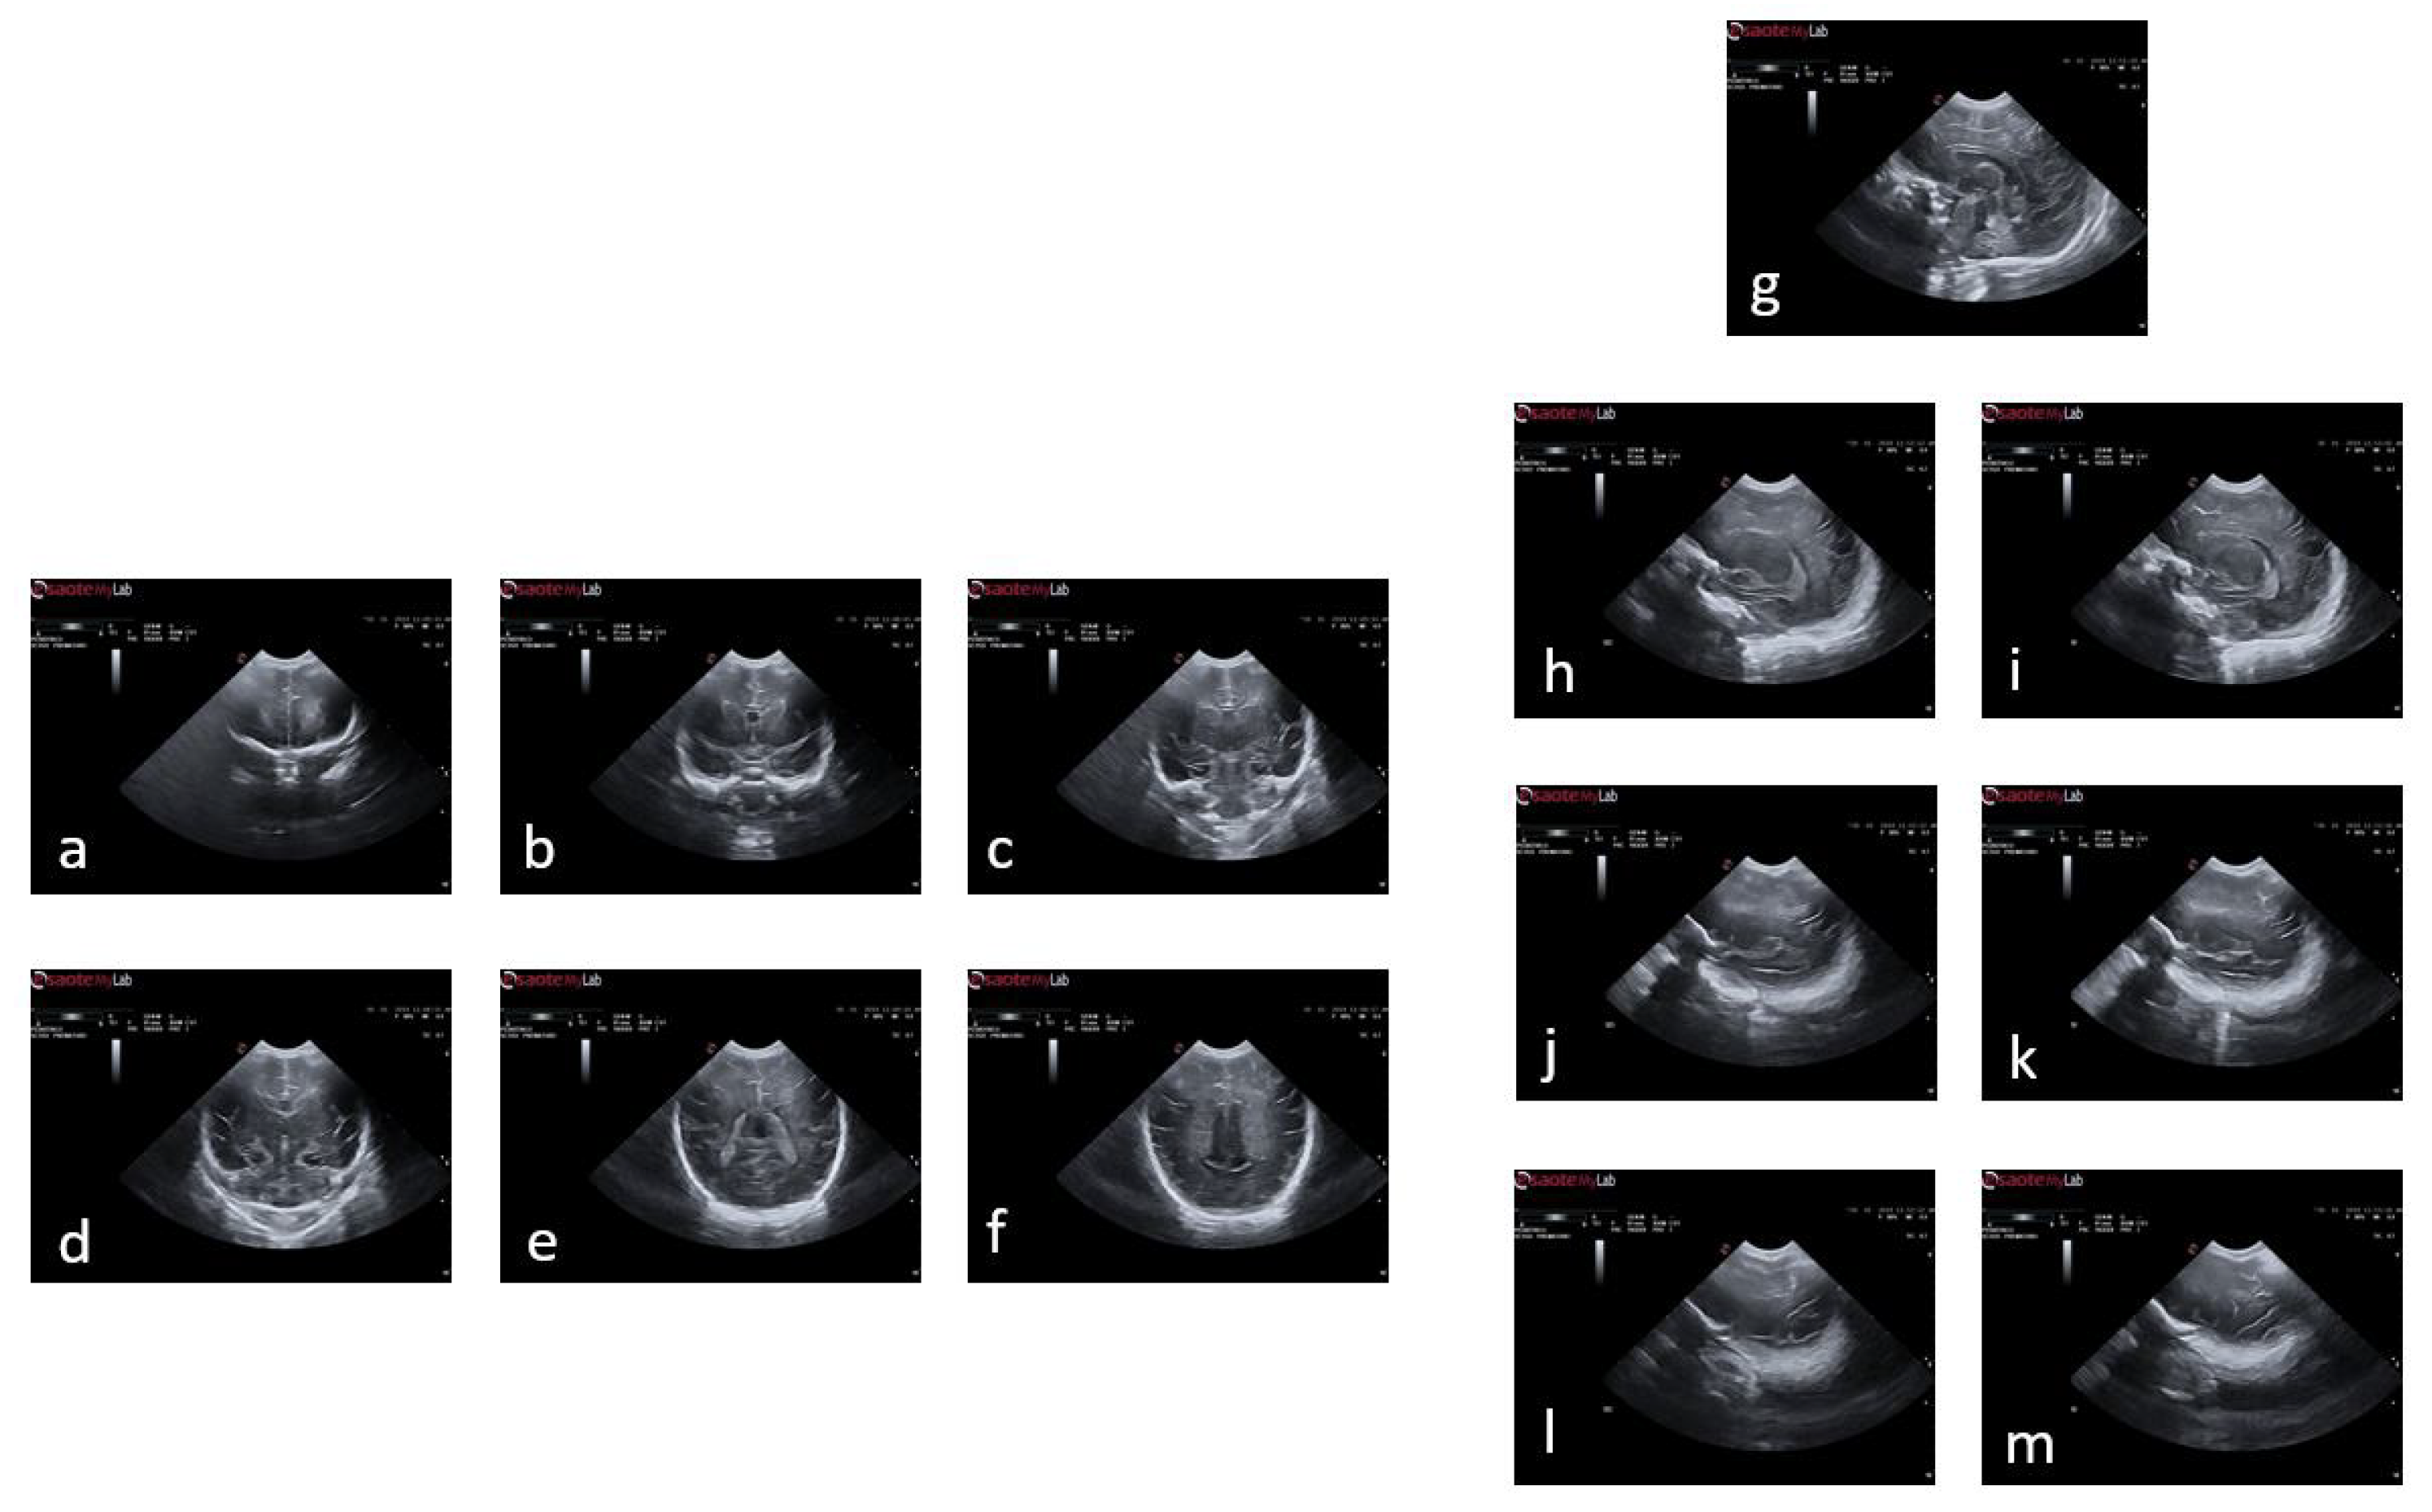

The neonatology department at Hospital Sant Joan de Déu has contributed a comprehensive brain ultrasound database. The database is organized into multiple sections, covering several weeks of examination. Two imaging planes, namely coronal (c1, c2, c3, c4, c5, and c6) and sagittal (s1, s2l, s2r, s3l, s3r, s4l, and s4r), were analyzed and included in the database (Figure 2). The timing in each case could vary depending on the clinical status of the infant. The final repository of images provided for the tool had more than 140 subjects of which 77 have been used for this study. Infants were excluded if they presented brain pathology at birth, intrauterine growth restriction, there were born from a multiple pregnancy or they presented genetic anomalies or major malformations. The original images provided by the clinicians are RGB images in BMP format measuring 800 pixels high and 1068 pixels wide. These images were pre-processed before being used in the application and converted into RGB images in JPG format measuring 550 pixels high and 868 pixels wide.

Figure 2. Plans used in the study of a premature baby. For the coronal plane and following the alphabetical order from a to f, we have the planes of c1, c2, c3, c4, c5 and c6; and following the same order but starting with g and ending with m, the sagittal planes s1, s2l, s2r, s3l, s3r, s4l and s4r.